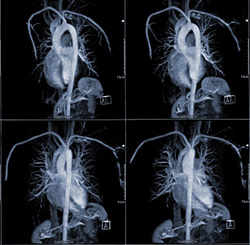

Получив результаты МРТ на диске, как посмотреть фотографии, знают не все . Многие пациенты считают, что для открытия файлов достаточно наличие компьютера . Это заблуждение .

Программа для просмотра КТ и МРТ снимков поможет не только посмотреть результаты исследований в домашних условиях, но и как можно быстрее отправить их лечащему врачу .

Как прочитать снимок МРТ . Магнитно-резонансная томография (МРТ) - метод исследования с использованием магнитного поля и компьютера для получения подробных изображений структуры мозга, позвоночника, костей и тканей . . .

Диск с мрт как посмотреть . МРТ позволяет получить изображение практически всех тканей тела . Ввиду того, что магнитно-резонансная томография дает очень детальное изображение, . В результате . . .

Как посмотреть диск мрт на компьютере . . . Обычно в программах для просмотра МРТ с одной стороны экрана есть большая черная область, а с другой - панель инструментов . . . . фото, лицензии . . .

Как посмотреть рентгеновский снимок на диске? Программы для открытия файлов КТ и МРТ . Чтобы открыть снимки с cd диска, Вам понадобится специальная программа — dicom-вьюер .

В центр лучевой диагностики часто поступают звонки с вопросом: "как посмотреть результаты исследований на . . .

Как посмотреть КТ снимки на компьютере Инструкция для тех, кто не знает как просмотреть снимки компьютерной томографии челюсти (CS 3D Imaging) на компьютере под управлением ОС Windows (XP, Vista, 7, 8) .